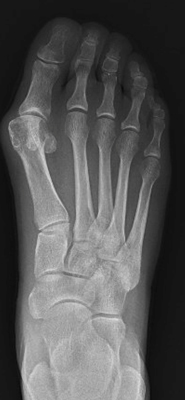

TOTAL ANKLE REPLACEMENT :: ORIF CALCANEUS :: ORIF ANKLE FRACTURE DISLOCATION :: COMPLEX BUNION AND LESSER TOE CORRECTION :: TALUS FRACTURE -1 :: TALUS FRACTURE -2 :: LISFRANC REPAIR :: COMPLEX TRIPLE ARTHRODESIS 1 :: COMPLEX TRIPLE ARTHRODESIS 2 :: MINIMALLY INVASIVE BUNION REPAIR 1 :: MINIMALLY INVASIVE BUNION REPAIR 2 :: ARTHROSCOPIC CARTILAGE REPAIR :: TENEX SPUR DEBRIDEMENT :: Haglunds Debridement and Achilles Repair